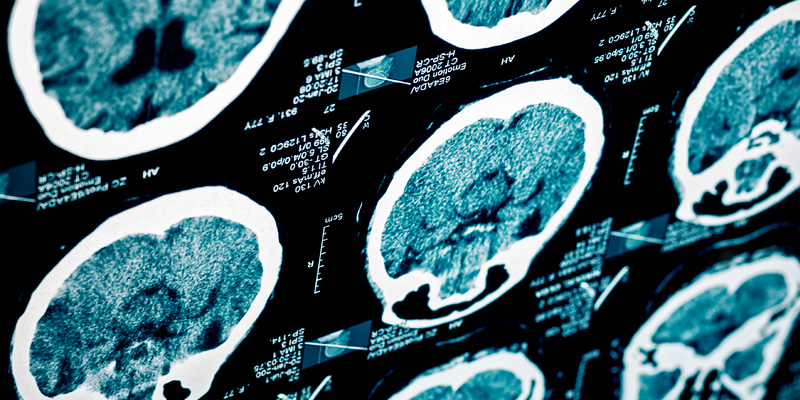

El servicio de neurocirugía realiza el manejo integral de patologías asociadas con el cerebro y la médula espinal (columna vertebral), con tecnología de última generación que permite aportar a la seguridad del paciente.

Trabajamos con tecnología actualizada en el área de neurocirugía como LEIKA, que permite obtener imágenes de alta calidad acompañadas con infrarrojos para patología vascular e identificar localización de tumores. También facilita la precisión en las cirugías.

Cirugía endoscópica y esterotaxia. Estamos especializados en recesión de tumores, con un grupo de expertos neuro-anestesiólogos, neuro-intensivistas, neuropsicólogos y neuro-fisiólogos que realizan cirugías de paciente despierto en busca de disminuir la morbilidad y la mortalidad de pacientes. Pioneros en cirugía de paciente despierto, sobre todo en lesiones cerca al área de lenguaje. Asociado a un grupo de neurooncología. Contamos con la última tecnología disponible para la recesión de tumores del Sistema Nervioso Central (SNC), con seguridad para el paciente.